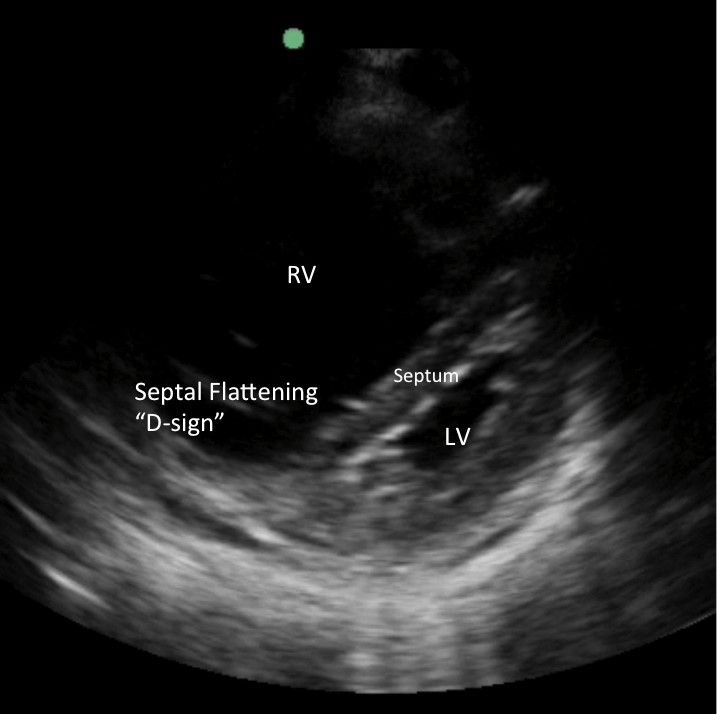

画像2. RHSは丸みを帯びた拡張したRVを示し、拡張期には心室間中隔が平坦になる(RV圧の上昇による「Dサイン」)